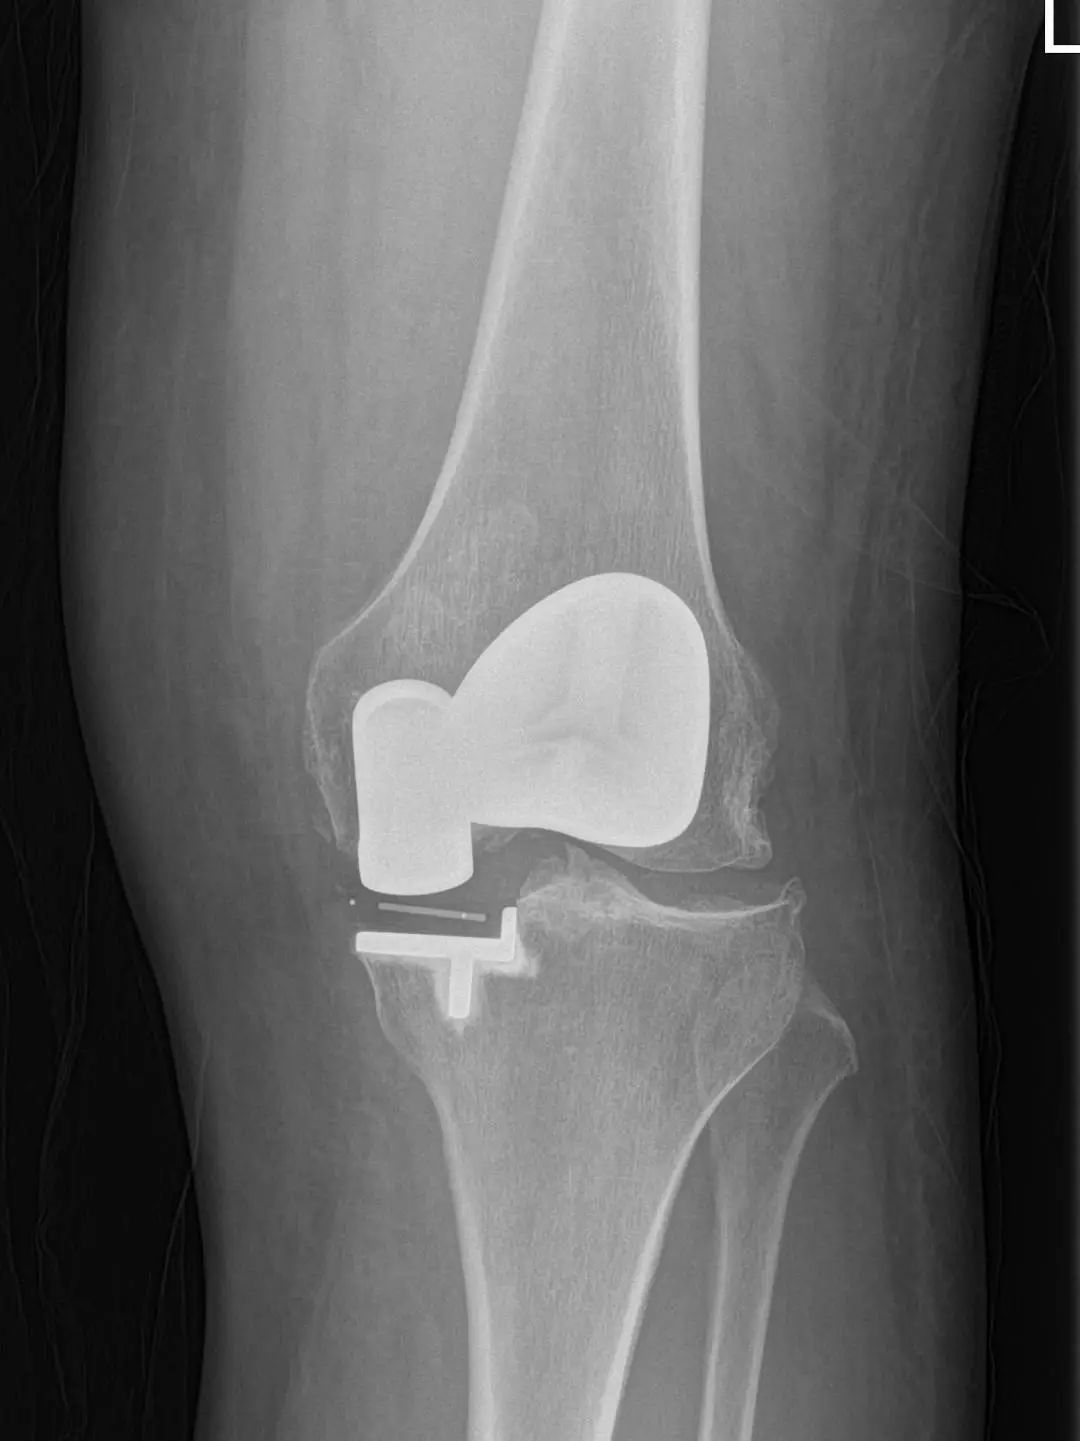

74岁的吕阿姨膝关节疼痛10余年,屈伸活动受限,外院就诊止痛药等保守治疗效果欠佳,拍片提示膝退行性骨关节炎。近日,她慕名来到上海市同济医院骨关节外科中心程飚主任门诊,程飚主任结合患者症状,影像学结果,体格检查,发现吕阿姨主要问题集中在膝关节内侧及髌股关节,膝关节外侧尚可。

为尽可能保留吕阿姨关节,程飚主任对定对吕阿姨进行膝关节部分置换手术,包括膝关节内侧单髁置换,髌股关节表面置换,尽可能减少膝关节截骨量,尽快恢复膝关节功能。吕阿姨术后第一天就开始下地走路了,她表示膝关节疼痛明显缓解,膝关节的活动范围也明显增加了,对程主任精准的手术治疗表示衷心的感谢。

部分膝关节置换手术目前已是非常成熟的治疗方法,亦属于保膝治疗的一种。主要包括单髁置换,髌股关节置换。单髁置换主要把膝关节内侧髁或者外侧髁表面已经磨损的部分替换成金属的假体和高分子聚乙烯耐磨垫片。髌股关节置换主要把髌股关节表面已经磨损的部分替换成金属的假体。

部分膝关节表面置换局限于膝关节病变部分,尽可能保留剩余健康部分关节,截骨量少,患者恢复快,损伤更小,完全保留了膝关节交叉韧带,本体感受更好。

同时有髌股关节及单侧髁的病变,可行单髁+髌股关节表面置换。